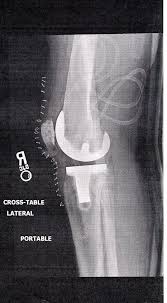

Knee replacement is a common procedure most often used to treat pain and disability caused by osteoarthritis.

Symptoms of a failed knee replacement there are a number of warning signs any person who has undergone knee replacement surgery should be aware of including a large amount of soreness or swelling in the affected joint. The first symptom is pain. Knee replacement is a surgical procedure in which the damaged or disease knee joint is replaced with an artificial prosthetic implant. Replaced knees can exhibit warmth in the joint for months after surgery but this effect steadily decreases over time.

Symptoms may include pain swelling stiffness and lack of stability. In addition to the swelling that can occur another symptom of a failing prosthesis can include noticeable warmth of the joint. There are few things that can increase the chances of successful knee replacement. Pain is never good and the purpose of getting a new knee in the first place is to relieve knee pain so that you can get back to work or back to enjoying a normal retirement.